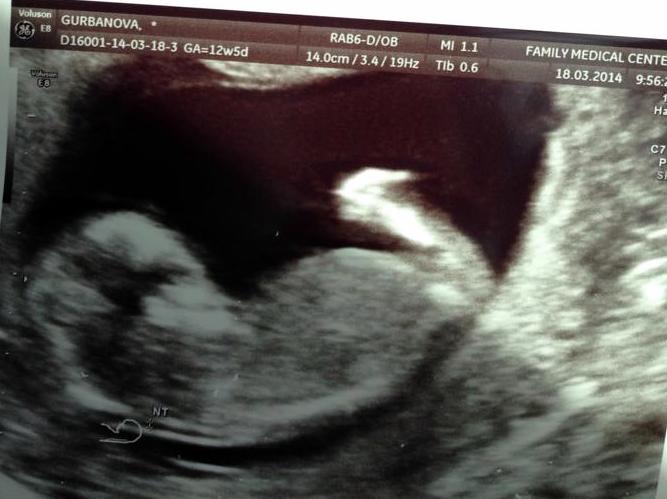

Наш первый скрининг!!! Здоровенький Малыш!!)))

Результаты: УЗИ, КТГ, доплера, скринингаНу вот, наконец дождалась ))С нетерпением ждала первый скрининг и вот он- малыш активничает в свои 13 неделек, Слава Богу никаких генет.отклонений-все в норме,

малыш наш уже от копчика до темени-целых 56мм, с ножками повыше))сердечко так мило билось, я чувствую что люблю своего малыша изо дня в день всё сильнее и сильнее..мое сердечко!!!

Пс. на фотике наше маленькое чудо (лежал спинкой к нам), на другом наконец и Я)))отмечу, что во время беременности ттт волосы тааак быстро растут))